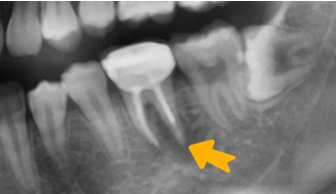

治療前:牙根尖發炎

治療前X光片

治療完成X光片